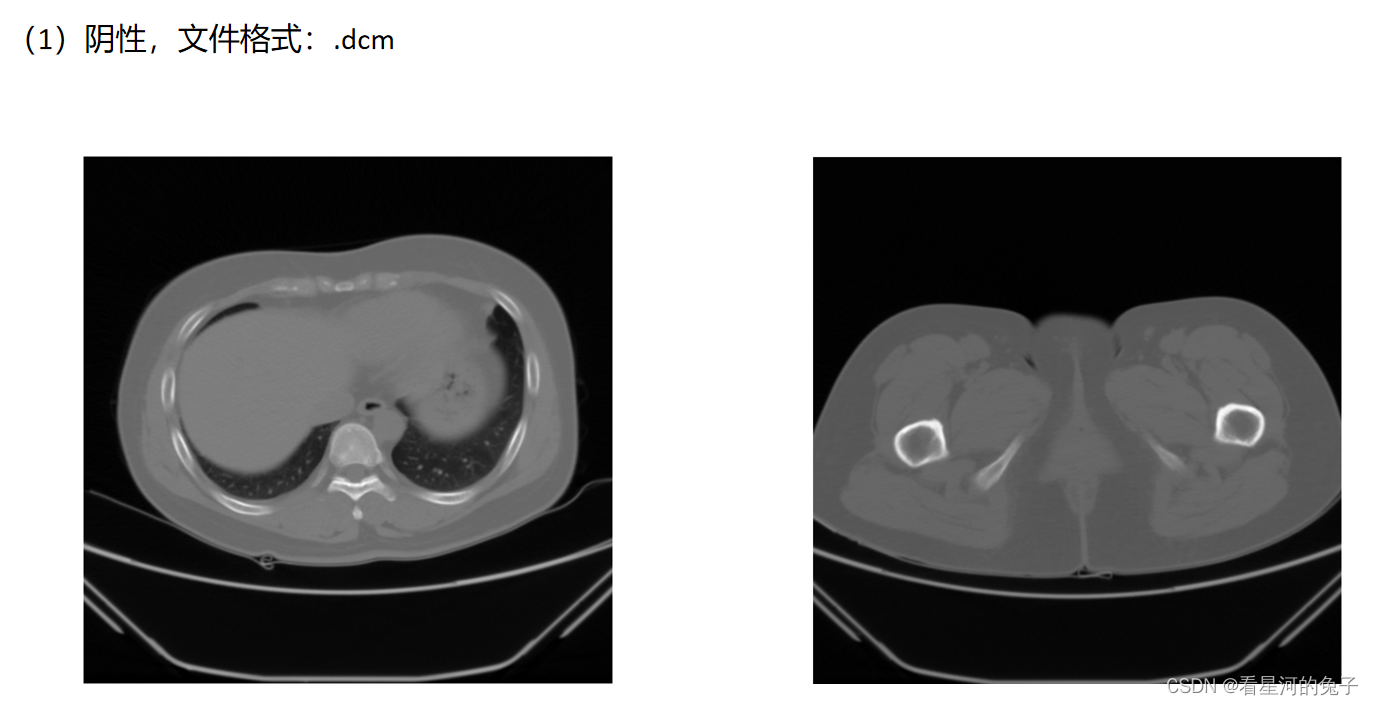

这里仅展示二维读取

结果展示